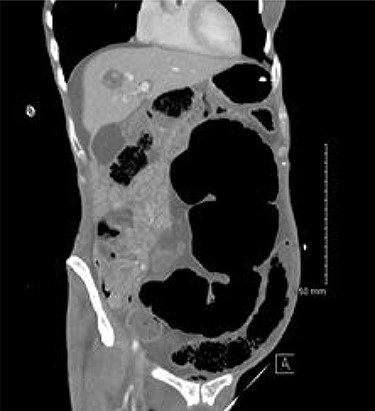

The patient continued to experience abdominal pain with multiple episodes of vomiting post-procedure. A wide-bore nasogastric tube was placed which drained 850 ml of bilious fluid. New onset tachycardia was noted and physical examination raised concerns for peritonitis. A further abdominal CT was performed which showed that the SV had been successfully decompressed but also revealed the presence of CV with proximal small bowel dilatation (Fig. 2). There was pneumatosis in the wall of the caecum which was distended to 10 cm in diameter, raising concerns for ischaemia and impending perforation. The patient was promptly transferred to the operating theatre for exploratory laparotomy.